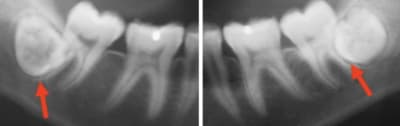

Bah alors ! Ben bien entendu qu’il faut les laisser en place ! Ça ne cause aucun problème...

8DE0A1E8-2DD0-4D53-A097-9BB4EBF20214_c1hzlx.jpg

AC10A55A-5FE5-4EEF-8BC3-48CE8E842DE0_wmi4kc.jpg

AB108EDA-34AF-4F84-AF10-998952ADDB29_ul6tfn.jpg

8243588C-A2F4-4BDC-B073-E1B3D70BBDF4_ok8qx5.jpg

E561E138-B7BA-4F34-AC1D-E238600B02A9_w4mrpg.jpg

27A0EF84-30D2-474C-B7F5-DD3F605A0909_zd09jn.jpg

ED7428F9-3851-4AF0-BDDB-192CED35661C_rcvw5y.jpg

En pièce jointe un patient qui n'a pas voulu écouter les consignes en 2014 et qui vient finalement de se faire opérer cette semaine.